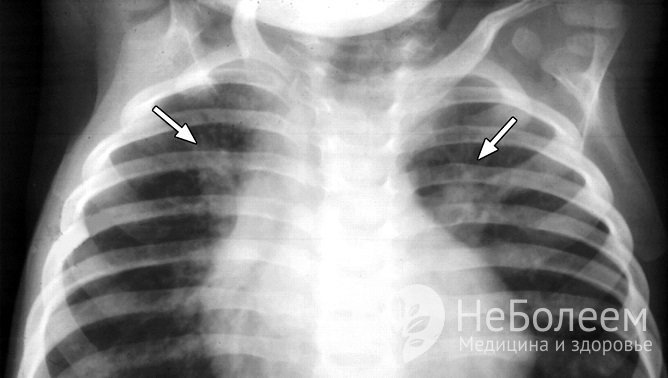

рентгенологическое исследование в прямой и боковой проекциях [наблюдаются умеренное усиление легочного рисунка (может отсутствовать при незначительном воспалении) и появление нечетких неоднородных инфильтративных теней];

Бронхопневмония на рентгеновском снимке

По показаниям выполняется полипозиционная рентгеноскопия. Контрольное рентгенографическое исследование проводится не ранее чем через 2-3 недели при неосложненной форме бронхопневмонии.